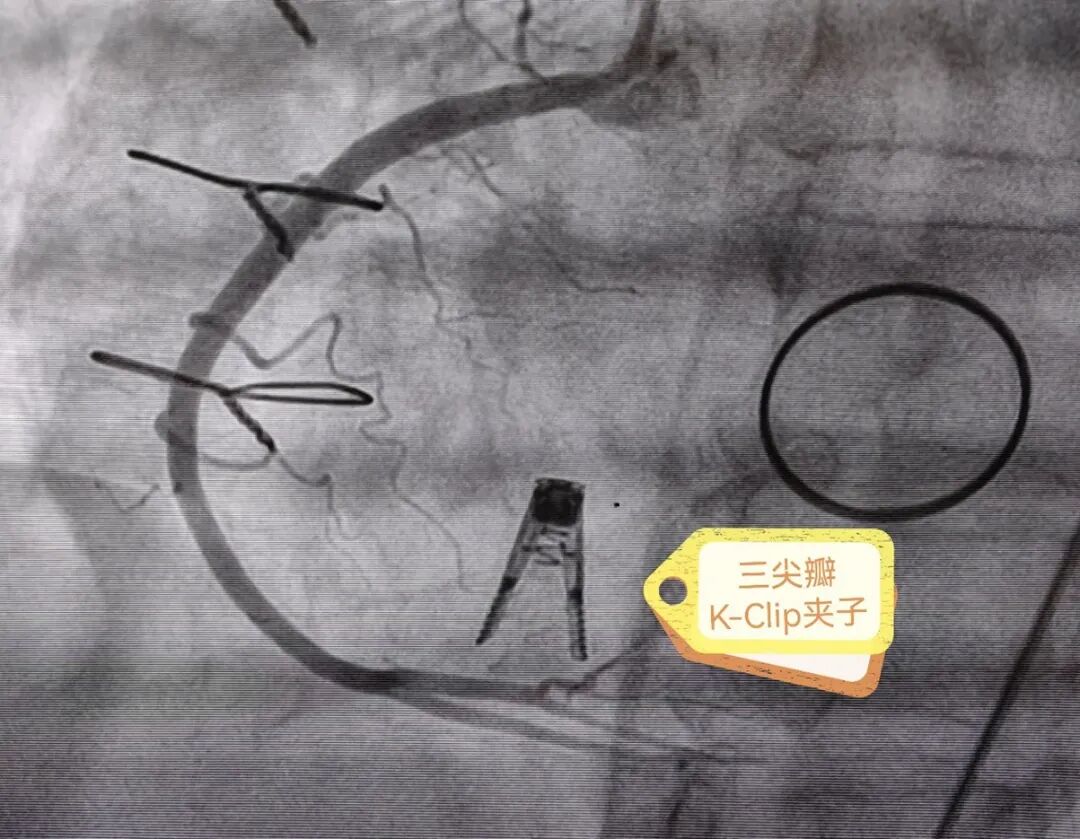

手术直播(十九):K-Clip经导管三尖瓣修复术

今日下午的最后一台手术由浙大一院心外科李伟栋教授团队担纲,为一位高危的三尖瓣重度反流患者成功进行了经静脉三尖瓣环修复术。

患者为一名70岁的老年女性,二尖瓣置换术9年,三尖瓣重度反流3年,伴有卵圆孔未闭、房颤10余年,心功能不全。经多学科讨论判定为传统外科手术高危患者,决定以K-Clip®为患者行经导管三尖瓣环成形术。

经过术前测量和分析,李伟栋教授团队结合患者的中央型反流伴有后隔长裂隙的情况定下手术策略,即在后瓣靠近隔瓣的位置,植入K-Clip®,进行后瓣偏隔瓣环的缩环成形,以期改善反流。

患者全麻后,右侧颈静脉穿刺,将K-Clip®输送系统送达右心房内。在超声医生指引下,将K-Clip®锚定件到位,打开夹持臂,对靶位进行夹合。

手术中,术者充分考虑了器械植锚定点须避免对冠脉和传导束的影响,适时地调整了手术策略,在后瓣与隔瓣交界处找到了理想的锚定靶点,仅用一枚K-Clip®夹子,就将三尖瓣反流从术前的重度(4级),下降为微量(0~1级),几乎没有反流。心脏团队和主持专家对反流减少程度非常满意,遂解离夹合件,退出输送系统。

术后评估冠脉血流通畅,生命体征稳定,伤口无出血,即结束手术。手术在30分钟的直播时间内完成。

K-Clip®是汇禾医疗自主研发的经导管三尖瓣环修复系统,复刻经典外科手术,经血管穿刺入路,不需要开胸、创伤小、恢复快、操作简单,使患者得到最大程度的获益。尤其是心外科有大量的瓣膜开胸术后患者,他们经过了主动脉瓣/二尖瓣术后,逐渐出现三尖瓣重度反流,却无法耐受第二次外科手术,生活质量低下甚至威胁生命。经血管的三尖瓣修复术,给他们带来了新的选择、新的希望。

浙大一院是全国使用K-Clip®最多例数的中心,目前已经成功完成39例,是K-Clip®的全国教学基地之一。